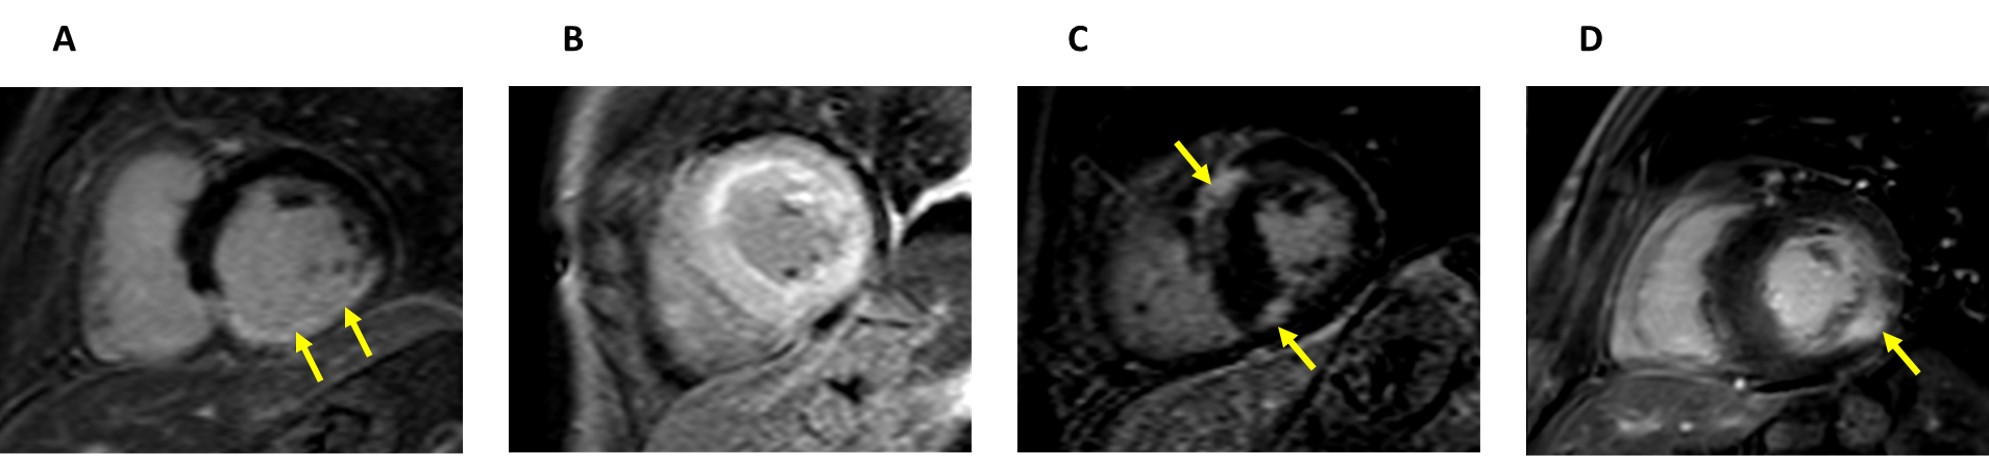

Fig. 6.Early stage Fabry disease. (A) Four-chamber cardiac magnetic resonance (CMR) image of a patient with early stage Fabry disease showing no left ventricular hypertrophy. (B) Short-axis late gadolinium enhancement CMR image demonstrating no late gadolinium enhancement. (C) Short-axis CMR T1 colour map demonstrating reduced T1 signal.

Fig. 7.Late stage Fabry disease. (A) Four-chamber cardiac magnetic resonance (CMR) image of a patient with late stage Fabry disease showing severe concentric left ventricular hypertrophy. (B) Short-axis late gadolinium enhancement (LGE) CMR image demonstrating extensive LGE in the basal inferolateral wall (arrow).